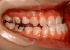

叢生 治療前 左側

いわゆる乱ぐい歯と言われていますが、八重歯もこの分類に属します。簡単に言えば、歯の大きさと顎の大きさにアンバランスがあり、並びきれないものです。形はいろいろなバリエーションがありますが、要は並びきれないので、顎を大きくするか歯を間引くかという治療方針になります。顎の骨を大きくすることもあるのですが、成長が付いて来られないとか、後戻りの危険性が大きいことなどから、歯を抜く方法が一般的です。

この患者さんでは、上下左右の歯を計4本抜きましたが、それでももスペースが足りませんので、さらに顎の形を変えて並べ替えました。

抜歯する歯は、変なところに生えていた犬歯ではなく、4番目の歯(=第一小臼歯)です。犬歯を抜くと、顎運動や歯並びの見た目、口元のふくらみがなくなることで老けて見えるなど、いろいろな悪影響があります。従って、できるだけ抜歯は避けたいのです。